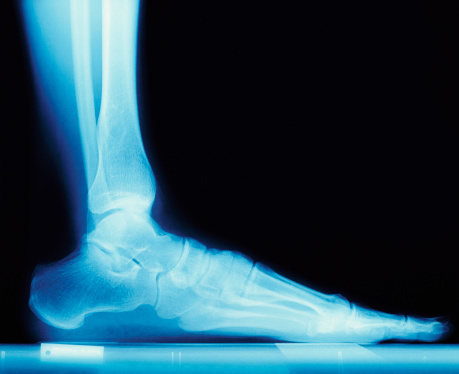

失眠会增加开发一些健康等并发症的风险记忆丧失,萧条,肥胖, 乃至心脏衰竭。新的研究还表明,睡眠障碍,如睡眠呼吸暂停和失眠可能会增加骨质疏松的风险。

研究发表在_睡眠医学_identified超过44000人谁被新诊断为睡眠障碍。研究发现:*那些用非呼吸睡眠障碍(如失眠)为2.76倍更容易患骨质疏松症的比没有睡眠障碍。

- 那些有呼吸暂停睡眠障碍是2.98倍更容易患骨质疏松症的比没有睡眠障碍。

发表在一个独立的,为期四年的研究美国杂志老年学会发现,人们谁睡了不超过六小时每晚都在骨质疏松症的风险较高。

即使考虑到年龄后,仍然在为那些用最短的睡眠持续风险显著增加。